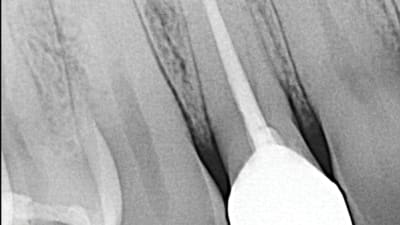

Implants Implantology Lateral Incisor Replacement Following Failed Endodontics By Paresh Patel, DDS January 01, 2021 2 min read